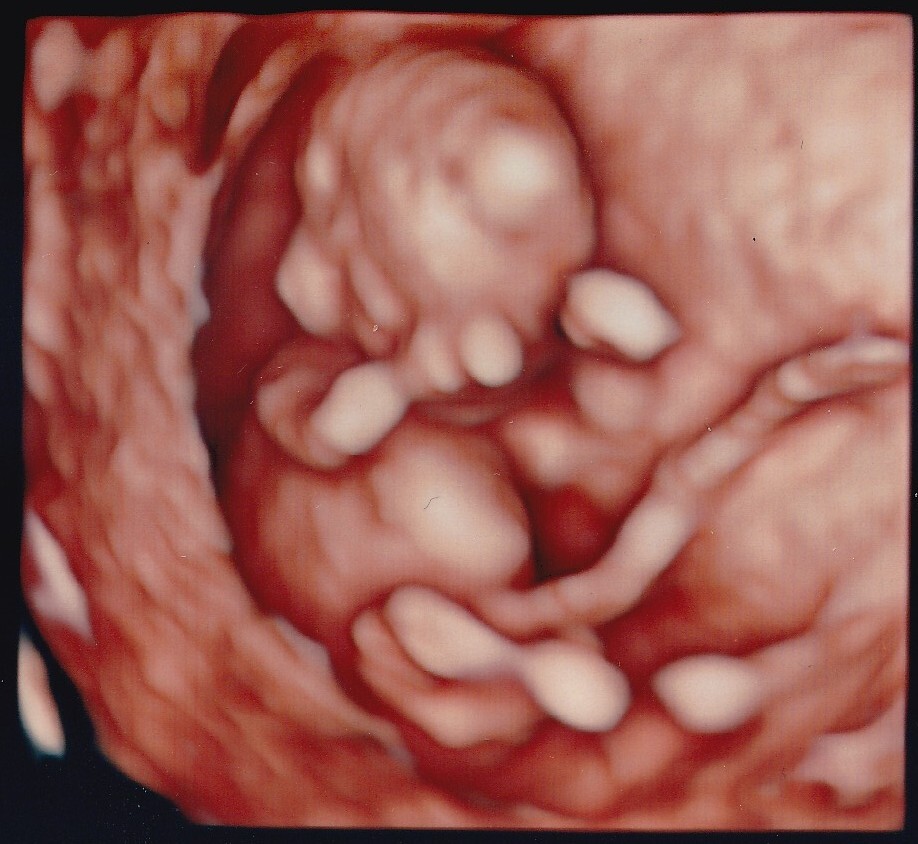

妊婦健診時の赤ちゃんの超音波画像記録について(ベビー動画館)

ご希望の方には「ベビー動画館」アプリをご利用いただき、お一人様ごと専用IDにてスマートフォンからいつでも健診動画をみることができます。